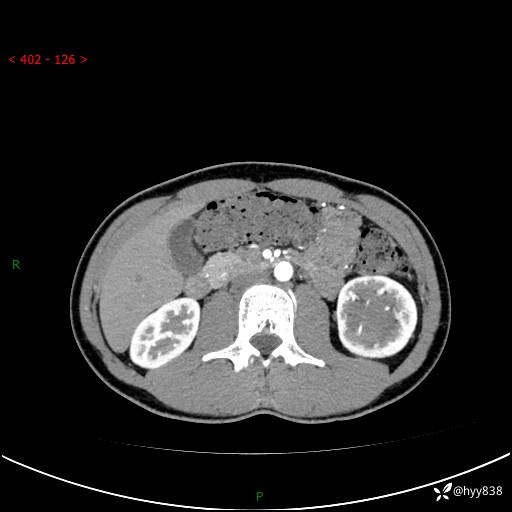

现病史:患者昨日中午进食后出现明显腹痛,腹泻,在我院急诊科行补液及对症治疗,双肾输尿管彩超提示左肾占位(5.2*4.3cm),平素无明显腰痛,无再发肉眼血尿等情况,现为求处理左肾占位,遂来我院,门诊以左肾占位收治入院。 患者起病以来,精神、食欲、睡眠尚可,大便可,小便如上,体力体重无明显下降。

双肾CT平扫+增强(三期)